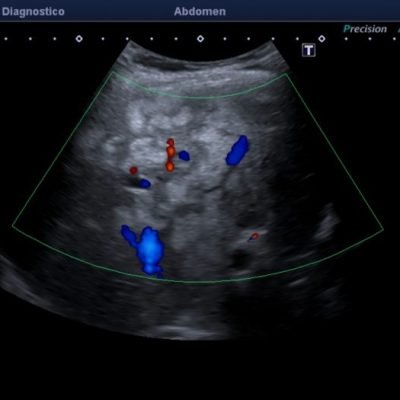

El médico de referencia le indica nueva ecografía de control, donde se observan múltiples y extensas lesiones focales hepáticas hiperecogénicas, redondeadas y confluentes, las cuales predominan en adyacencia a venas supra hepáticas, sin condicionar efecto de masa y sin alteración de la superficie hepática(fig. 1 y 2). Ante la valoración con Doppler color no presenta patrón de flujo peri ni intralesional y respeta el calibre de las venas supra hepáticas(fig. 3 y 4). Dada las características ecográficas se sospecha esteatosis focal multinodular confluente como principal diagnóstico presuntivo, siendo los diagnósticos diferenciales patologías de naturaleza infecciosa, tumoral o metastásica.